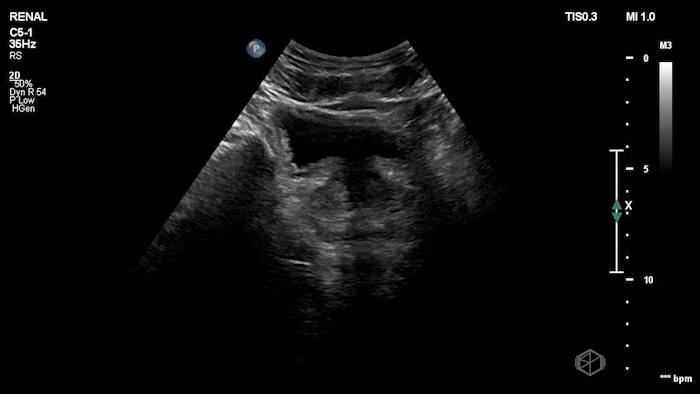

15 - What grade of hydronephrosis is this?

Severe hydronephrosis, cortical wall thinning is present.